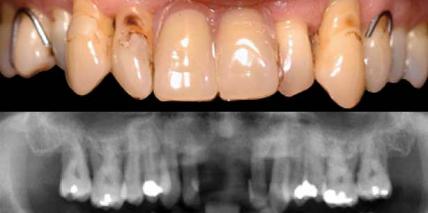

Implantologische Lösungen für komplexe parodontale Probleme

Komplexe implantologische Lösungen für komplexe parodontale Probleme

Jahr 2014, Ausgabe 03, Seite 4 Autoren: Univ.-Prof. Dr. Dr. Georg Watzek und Dr. Rudolf Fürhauser